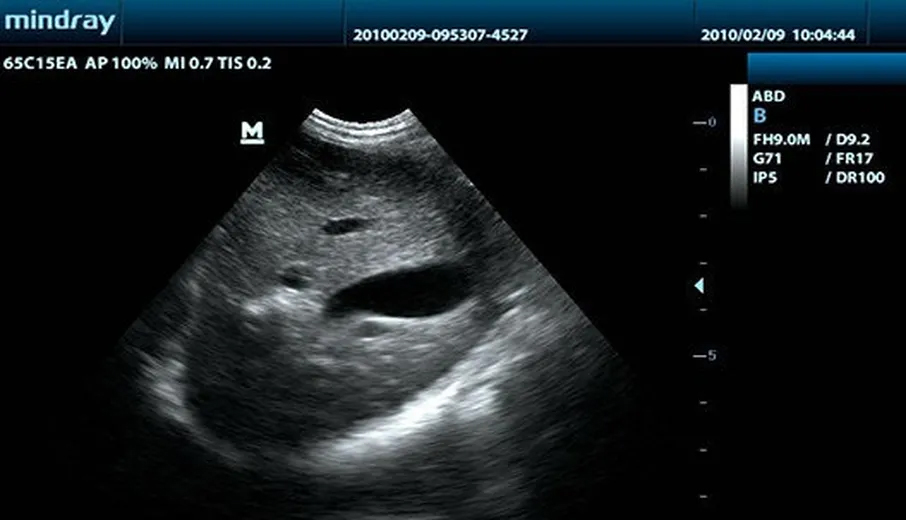

Клинические изображения

Хорошее качество изображения, удобная организация рабочего процесса и незначительный вес являются достоинствами УЗ-сканера DP-10 Vet, черно-белой ультразвуковой системы нового поколения от компании Mindray. С новой платформой, базирующейся на мощном процессоре Intel, УЗИ аппарат обеспечит вам дополнительные возможности ультразвукового исследования.

Используя дополнительные гармоники, генерируемые в тканях пограничных слоев, ТГ значительно повышает контрастное разрешение и улучшает качество изображения, особенно для технически сложных объектов.